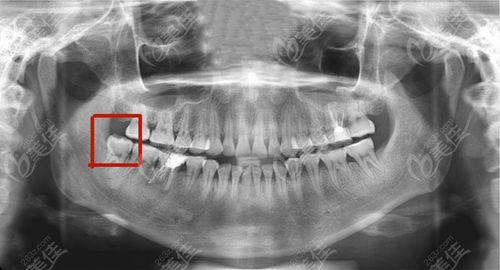

正位智齿,正位智齿图片

正位智齿图片

正位智齿长什么样子

智齿拍片

阻生智齿

智齿x光片

阻生智齿图片